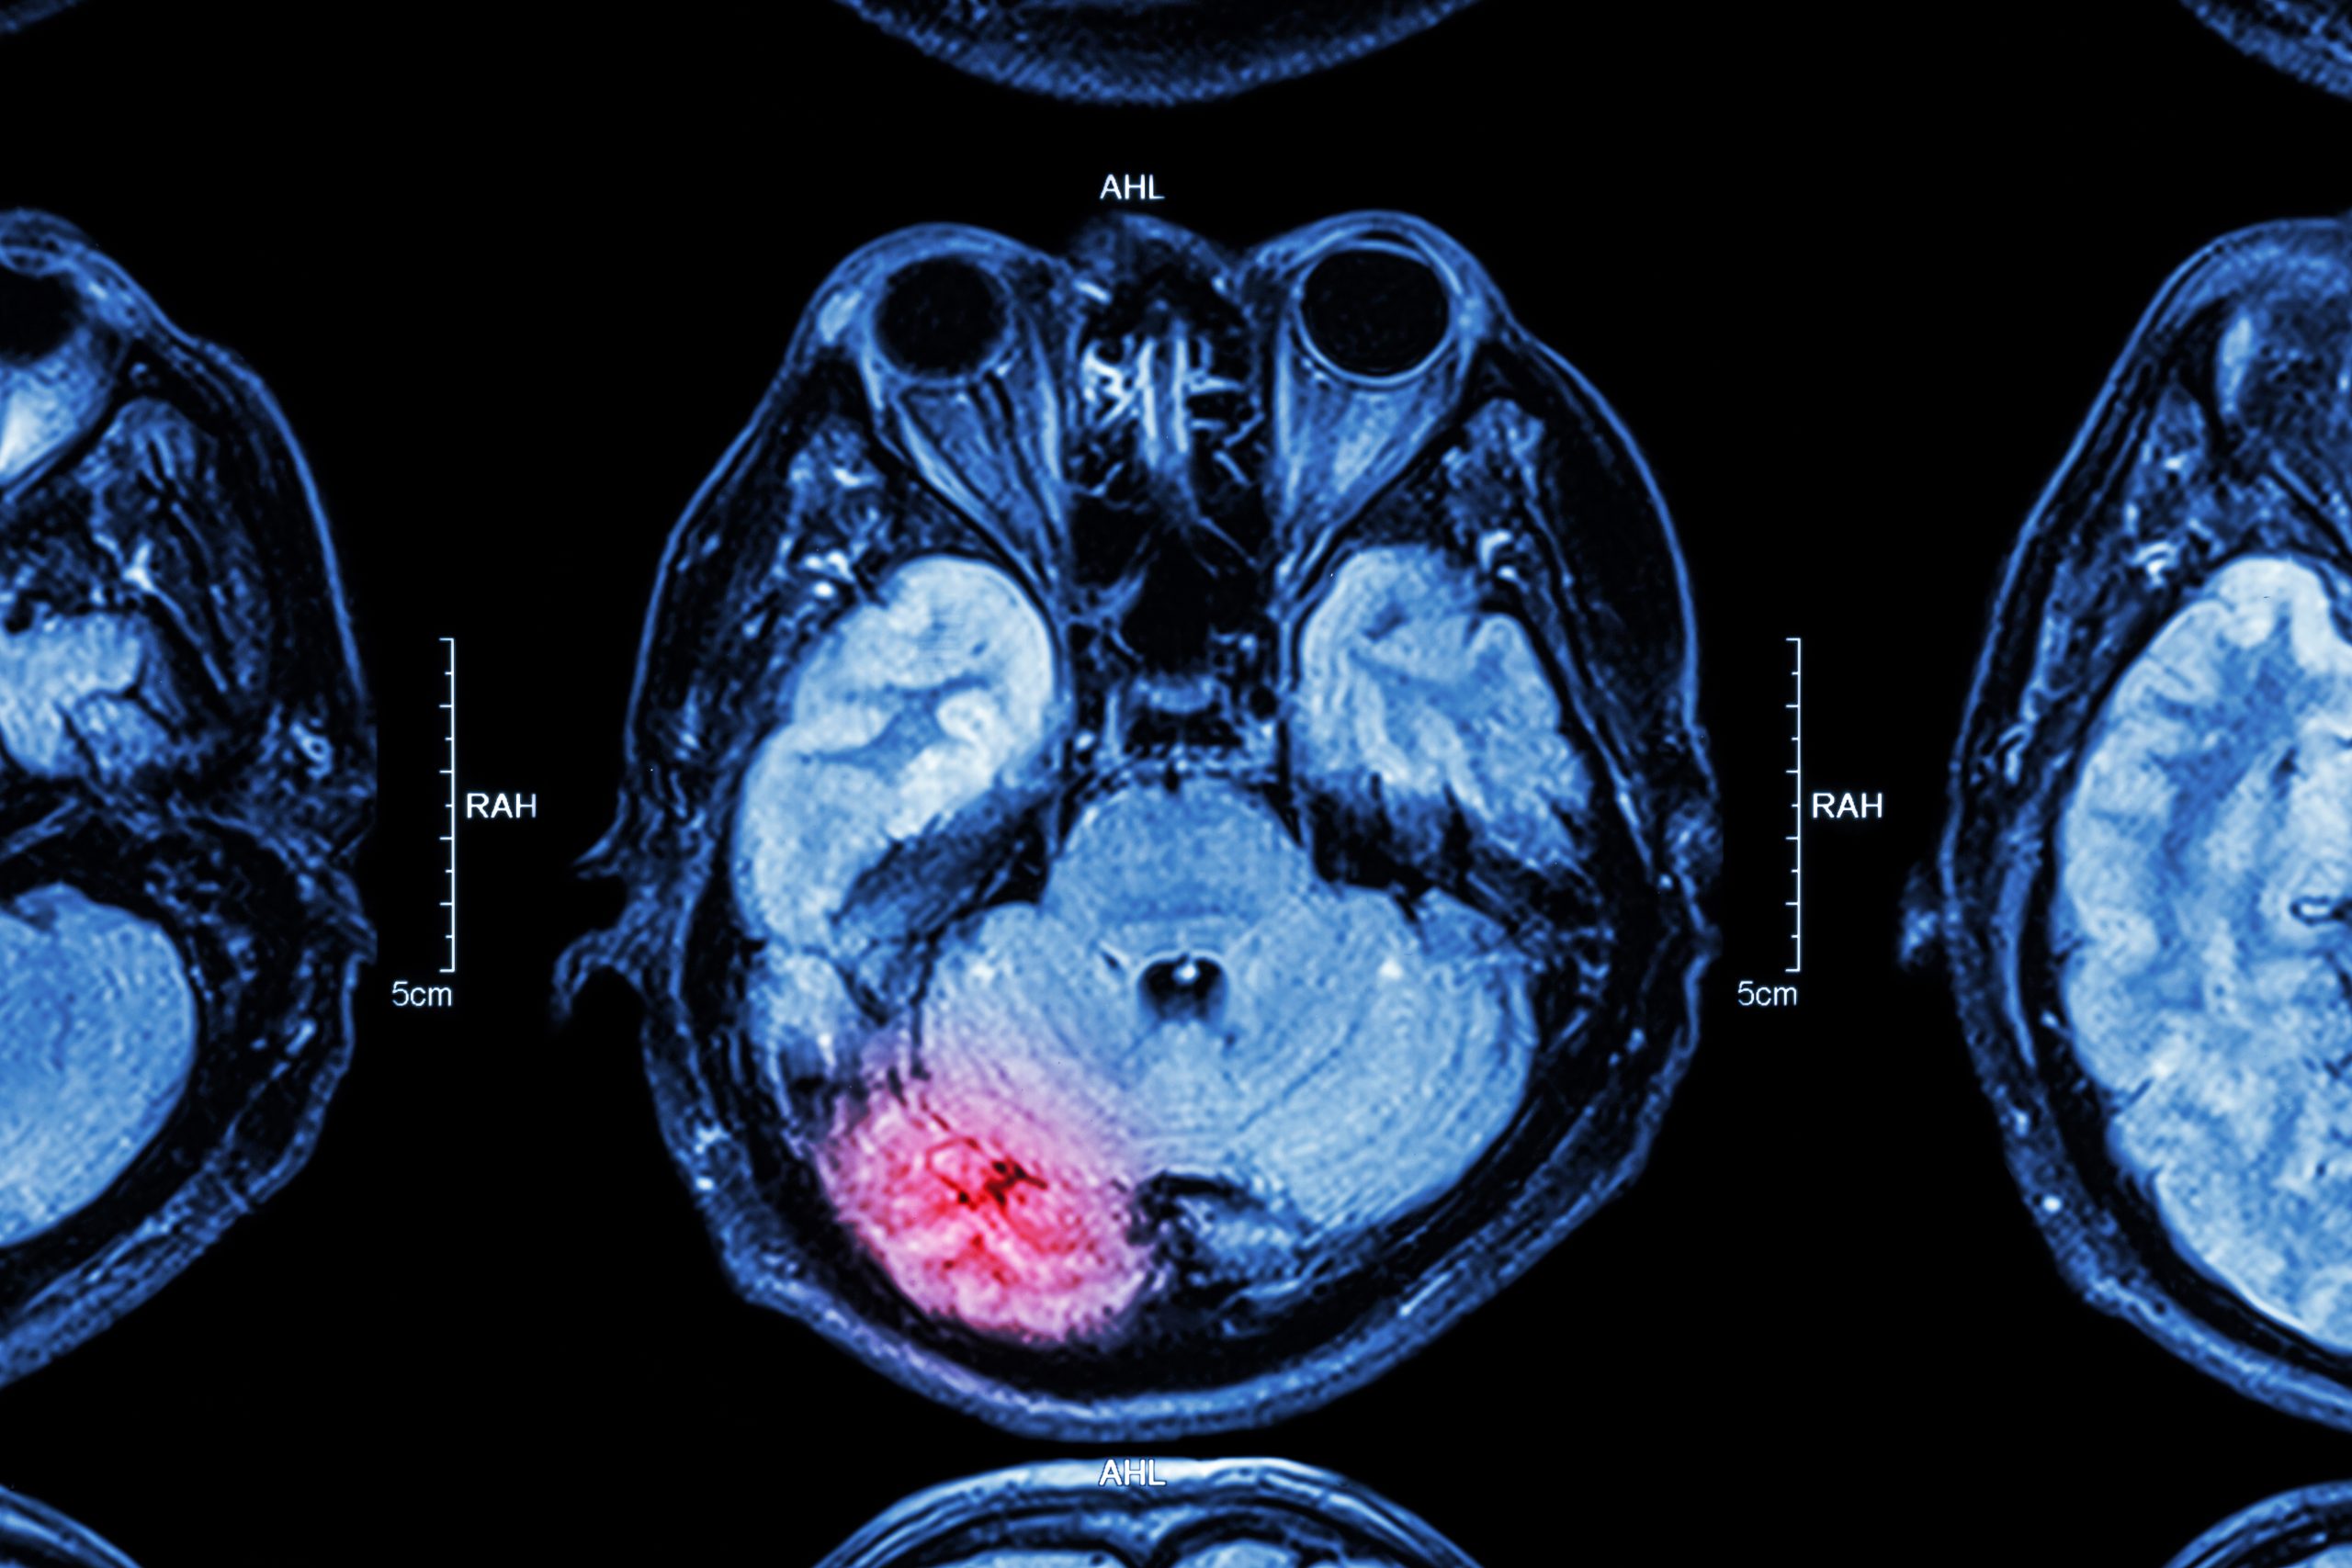

From sdbif.org

MRA Archives San Diego Brain Injury Foundation What Can An Mri Detect For Nerve Damage  It can help diagnose nerve abnormalities, such as. Mri can help diagnose peripheral nerve injury by providing detailed images of the nerves and surrounding tissues. An mri scan can show nerve damage caused by injury, compression, or tumor, but it may not detect all types of nerve problems. Learn how mri scan can show structural lesions that may be pressing. What Can An Mri Detect For Nerve Damage.

From aica.com

Here’s How an MRI Can Find Brain Damage AICA Orthopedics What Can An Mri Detect For Nerve Damage  Mr neurography (mrn) is a technique that images nerves anywhere in the body using mri scanners. Mri uses a magnetic field and radio waves to produce detailed images of areas affected by nerve damage. Learn how mri scans work, what they can and cannot. Conventional mris can sometimes show nerve abnormalities, but mr neurography imaging is more sensitive, since it. What Can An Mri Detect For Nerve Damage.